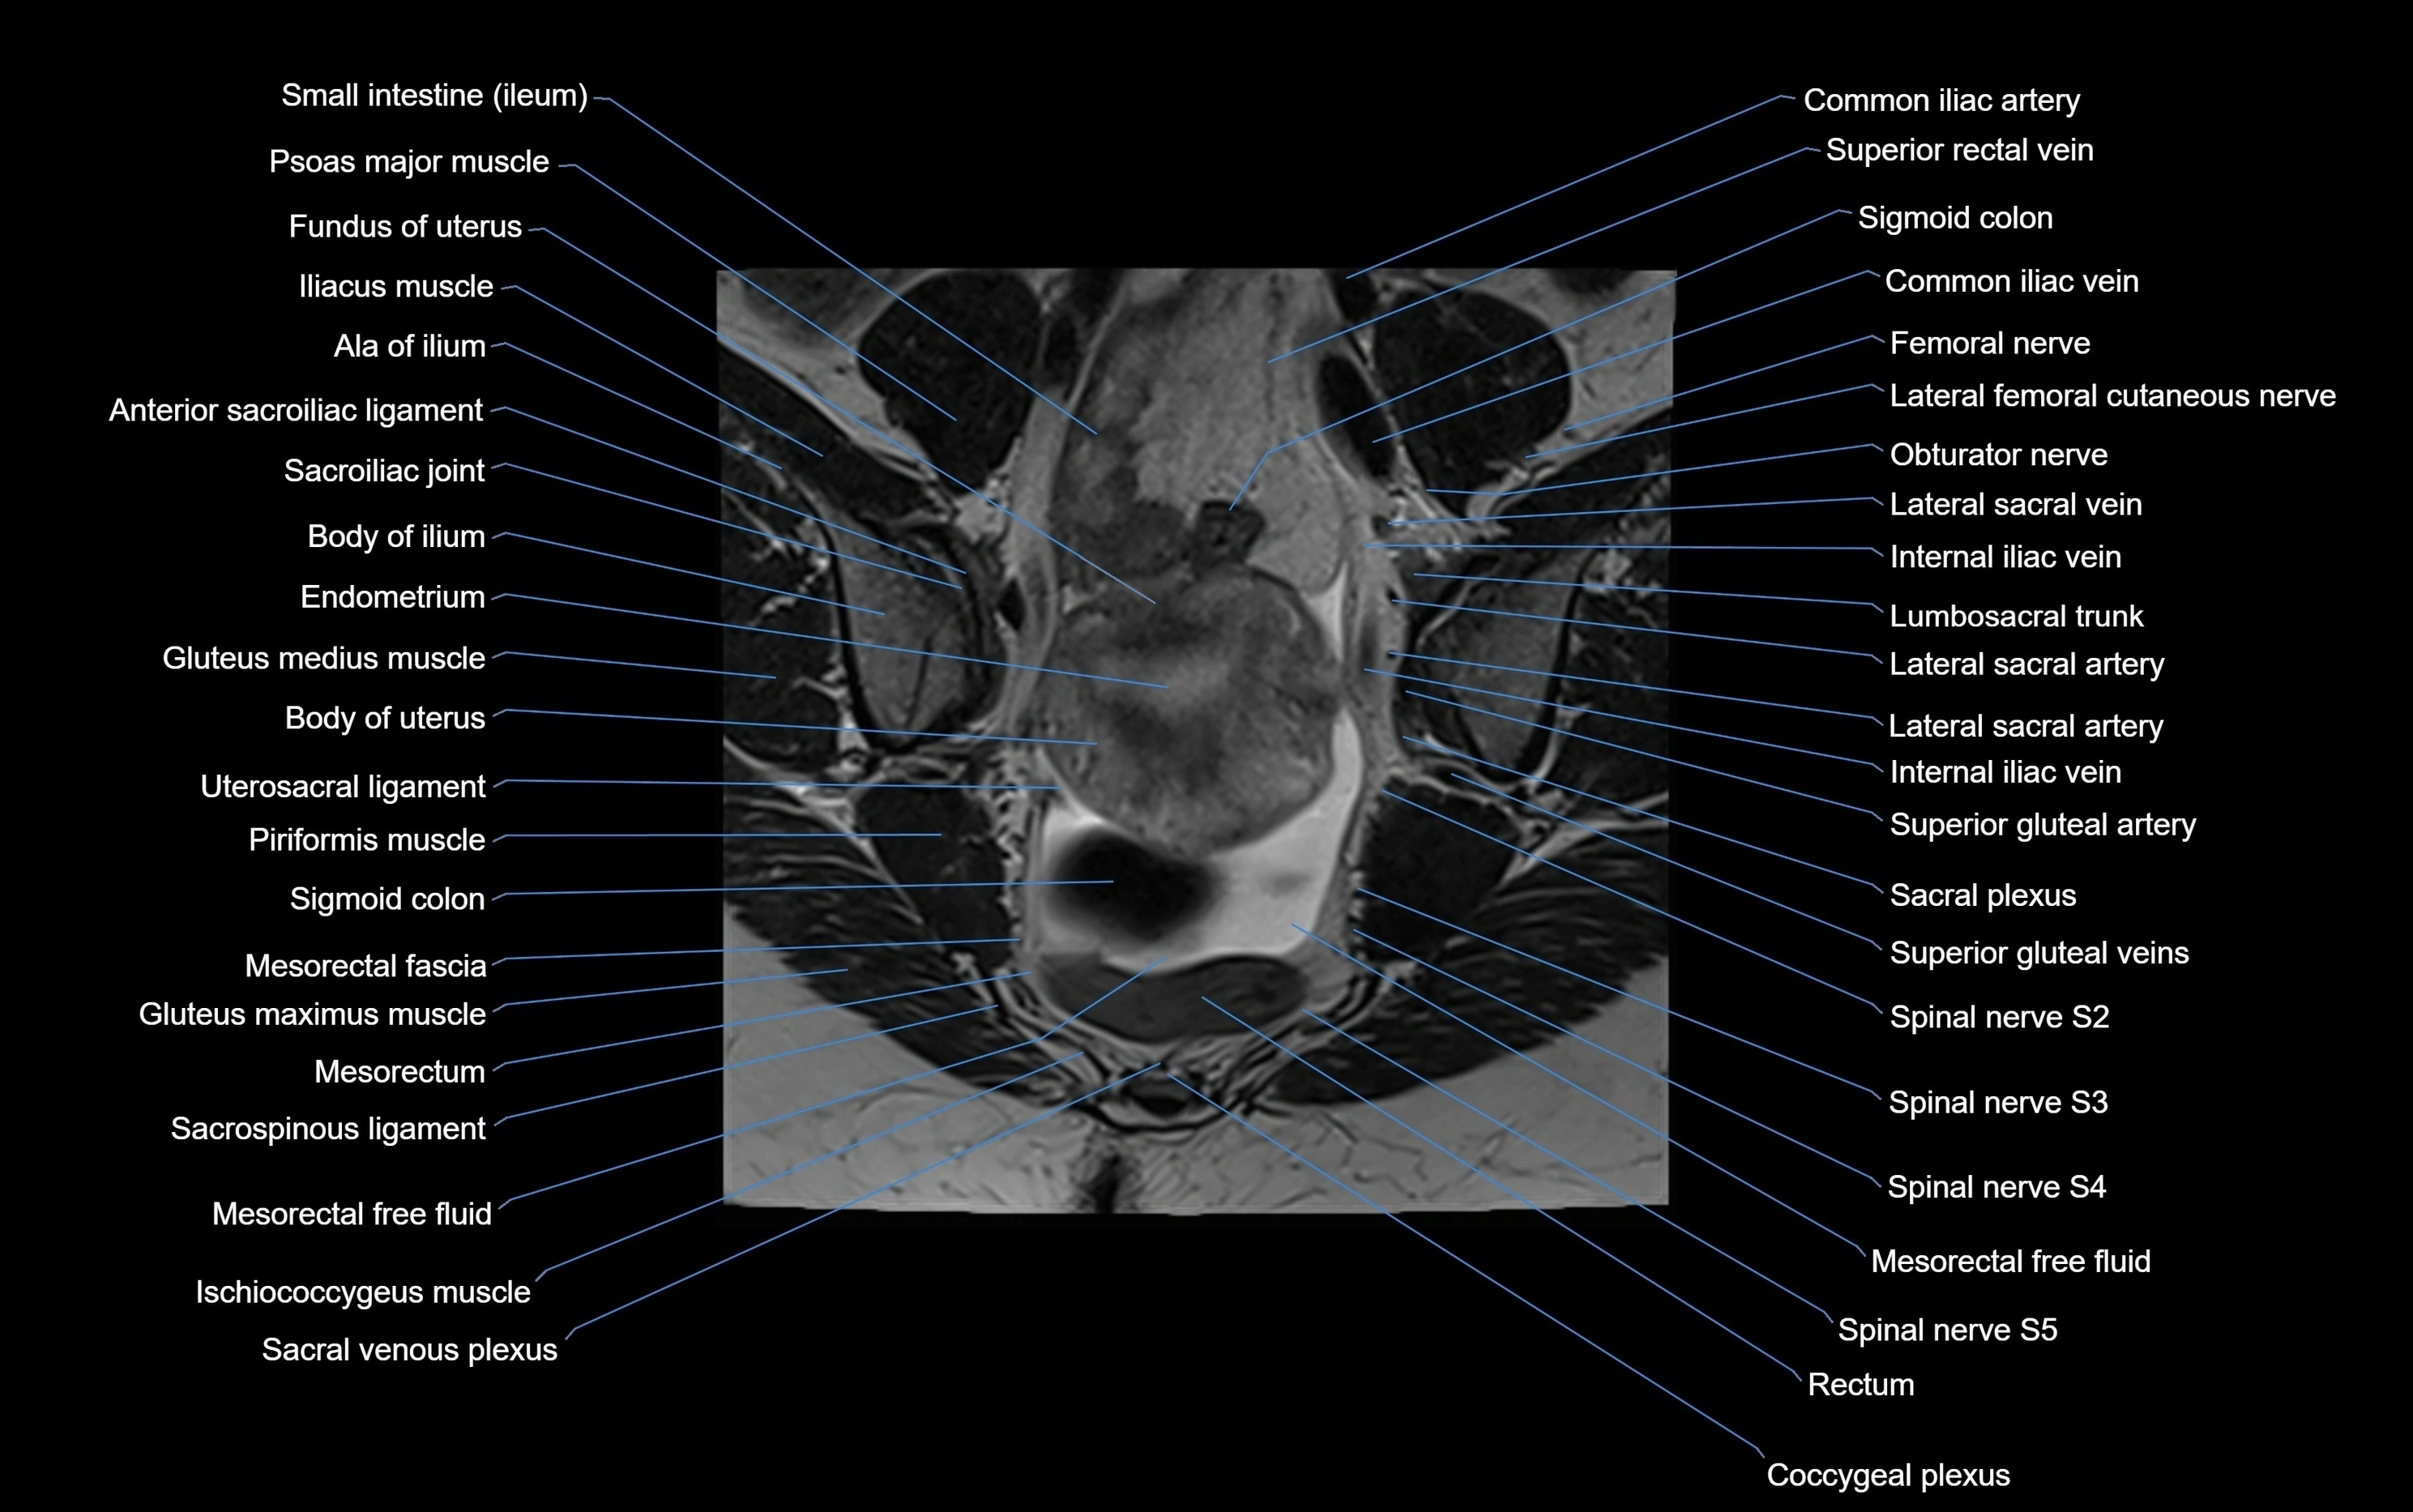

CT image

image